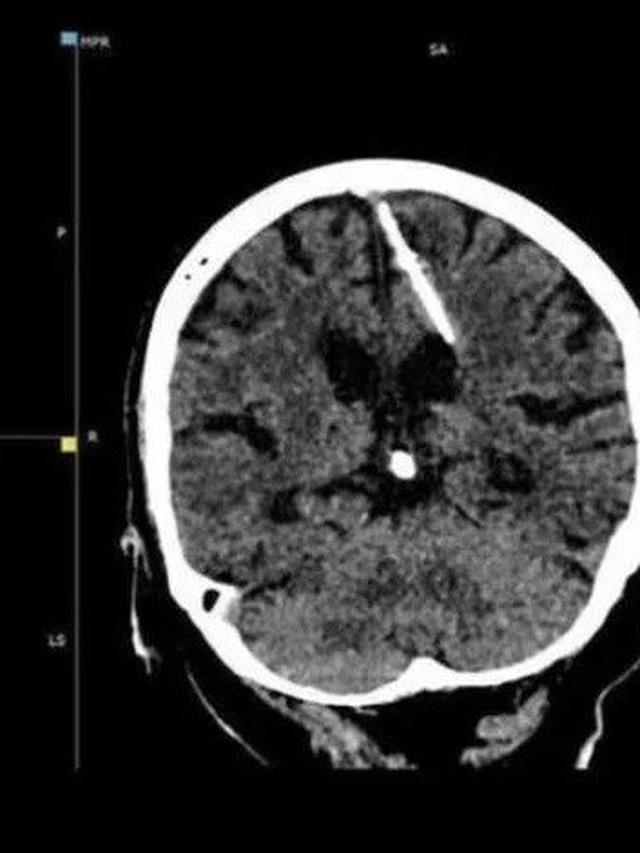

Liputan6.com, Jakarta Seorang wanita berusia 80 tahun dari wilayah Sakhalin, Rusia, baru-baru ini membuat penemuan yang mengejutkan setelah menjalani CT scan. Hasil pemeriksaan tersebut mengungkapkan adanya jarum logam berukuran 3 cm yang tertancap di sisi kiri otaknya.

Kementerian Kesehatan Sakhalin telah merilis foto hasil CT scan wanita tersebut, yang disertai dengan penjelasan yang membingungkan. Mempertimbangkan usia wanita tersebut, para dokter meyakini bahwa jarum tersebut dimasukkan ke dalam otaknya oleh orang tuanya sendiri segera setelah dia dilahirkan.

Para dokter yang merawatnya telah menyimpulkan bahwa intervensi bedah untuk mengangkat jarum logam tersebut akan membahayakan pasien, mengingat usianya yang sudah lanjut.

Oleh karena itu, mereka menyimpulkan bahwa jarum suntik tersebut tidak menimbulkan ancaman bagi kesehatannya, dan wanita tersebut akan melanjutkan hidupnya seperti biasa. Namun, dia akan tetap berada di bawah pengawasan ketat dokternya.